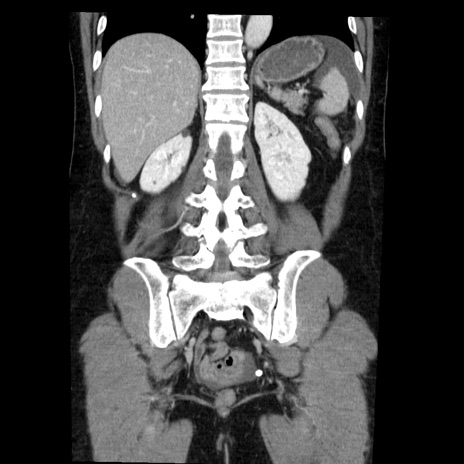

症例6(冠状断像)

【症例】50歳代女性

【主訴】下腹部痛

【既往歴】卵巣癌術後(8年前に当院で卵巣摘出)

【身体所見】 意識清明、腹部:平坦、腸蠕動音→、やや硬、下腹部自発痛・圧痛あり、反跳痛あり、筋性防御なし。

【データ】WBC 16000、CRP 0.01